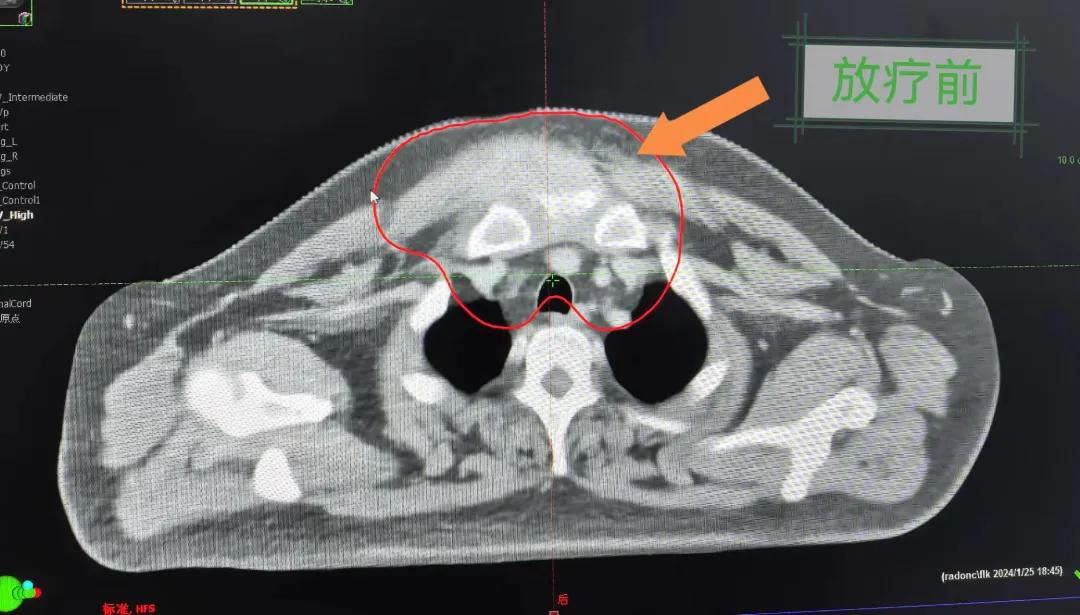

2個月前,市二院放療科接診了一名特殊的病人。一位40歲的中年男人,其前胸部竟然長了一個巨大的大腫塊,已有8cm左右且疼痛。

患者經(jīng)多方咨詢與打聽,在家屬的陪同下來到市二院放療科找到趙亮主任尋求幫助。入院后迅速完善了相關(guān)檢查,診斷為罕見的“胸壁腫瘤”。因腫瘤體積大,侵犯周圍組織,手術(shù)治療難度較大,經(jīng)院內(nèi)多學科會診后,決定采用無創(chuàng)的局部放射治療。在初步告知患者及家屬治療方案時,病人及家屬都擔心預(yù)后及放療可能引起的不適,趙亮主任詳細且耐心的向家屬和病人講述放療過程中可能出現(xiàn)的不良反應(yīng),確保讓他們安心治療。

隨后,趙亮主任帶領(lǐng)放療團隊以最快的速度完成了患者的放射治療計劃,在保證放療精準打擊腫瘤的同時,利用先進的三維立體精確放療技術(shù),最大限度的避免心臟、肺部的損傷發(fā)生,整體治療精準度達到1mm以內(nèi)。經(jīng)過10次的放射治療后,患者疼痛已明顯減輕,胸部腫物肉眼可見的縮小,患者及家屬臉上終于露出久違的笑臉。

治療期間,患者沒有出現(xiàn)明顯不適,治療結(jié)束后,患者胸壁腫物由最初8cm縮小至約1cm,后患者至外科行手術(shù)治療。